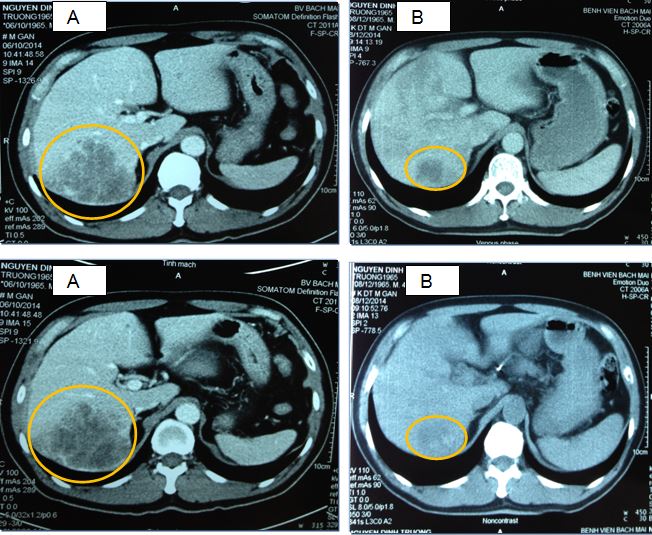

Chụp MSCT ổ bụng

Hình 1: Hình ảnh khối u hạ phân thuỳ 6 gan phải, kích thước 8,5 x7,2 cm, khối u gan trái 3,1 x2,1 cm

Hình 4: Hình ảnh khối u trước điều trị 7,0 x 8,6 cm (A) và sau điều trị 3,0 x 3,5cm (B)